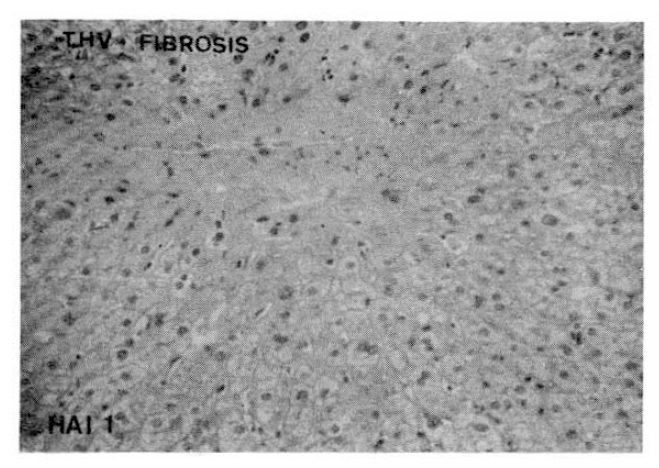

3. Portal Fibrosis or Terminal Hepatic Vein Fibrosis

Higher indices of portal fibrosis, such as bridging or precirrhotic changes, were more prominent in the CAH-B group (68.4%) than in the CAH-C group (42.1%). Perivenular or perihepatocellular fibrosis was noted frequently in both groups (63.2% in CAH-C and 78.9% in CAH-B group respectively), but there was no significant difference in the morphologic feature of terminal hepatic vein fibrosis between these two groups (Table 5,6, Fig. 3,4,).

Portal Fibrosis

Terminal Hepatic Vein Fibrosis

Fig. 3.

Histopathologic appearance of portal fibrosis, expansile (HAI 1, left) and precirrhotic portal fibrosis (HAI 4, right).

Fig. 4.

Histopathologic appearance of terminal hepatic vein fibrosis, perivenular (HAI 1).